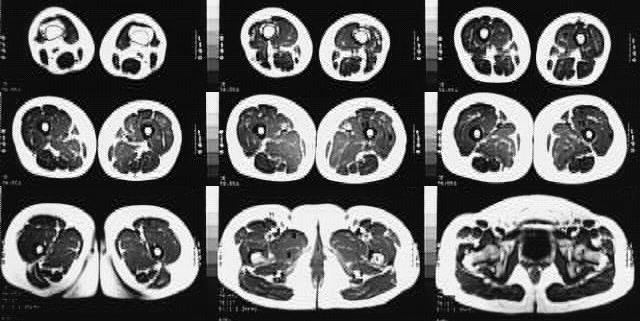

Lower Limbs: Thigh MRI Cross